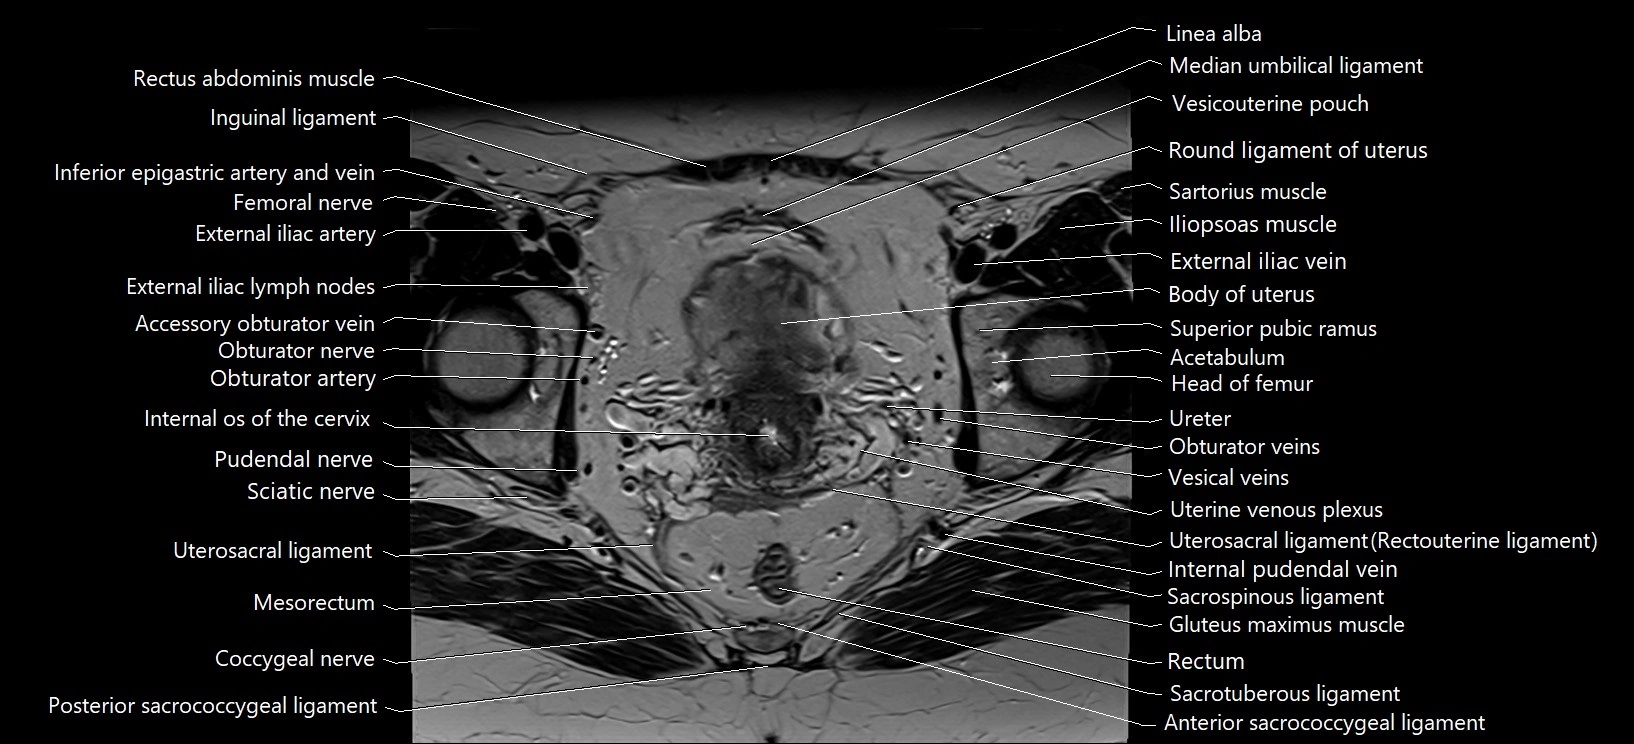

- Acetabulum

- Body of uterus

- External iliac artery

- External iliac lymph nodes

- External iliac vein

- Femoral nerve

- Head of femur

- Inguinal ligament

- Internal os of the cervix

- Internal pudendal vein

- Linea alba

- Median umbilical ligament

- Mesorectum

- Obturator artery

- Obturator externus muscle

- Obturator internus muscle

- Obturator nerve

- Obturator veins

- Pudendal nerve

- Rectum

- Round ligament of uterus

- Sacrospinous ligament

- Sacrotuberous ligament

- Sciatic nerve

- Superior pubic ramus

- Uterine venous plexus

- Uterosacral ligament

- Vesicouterine pouch